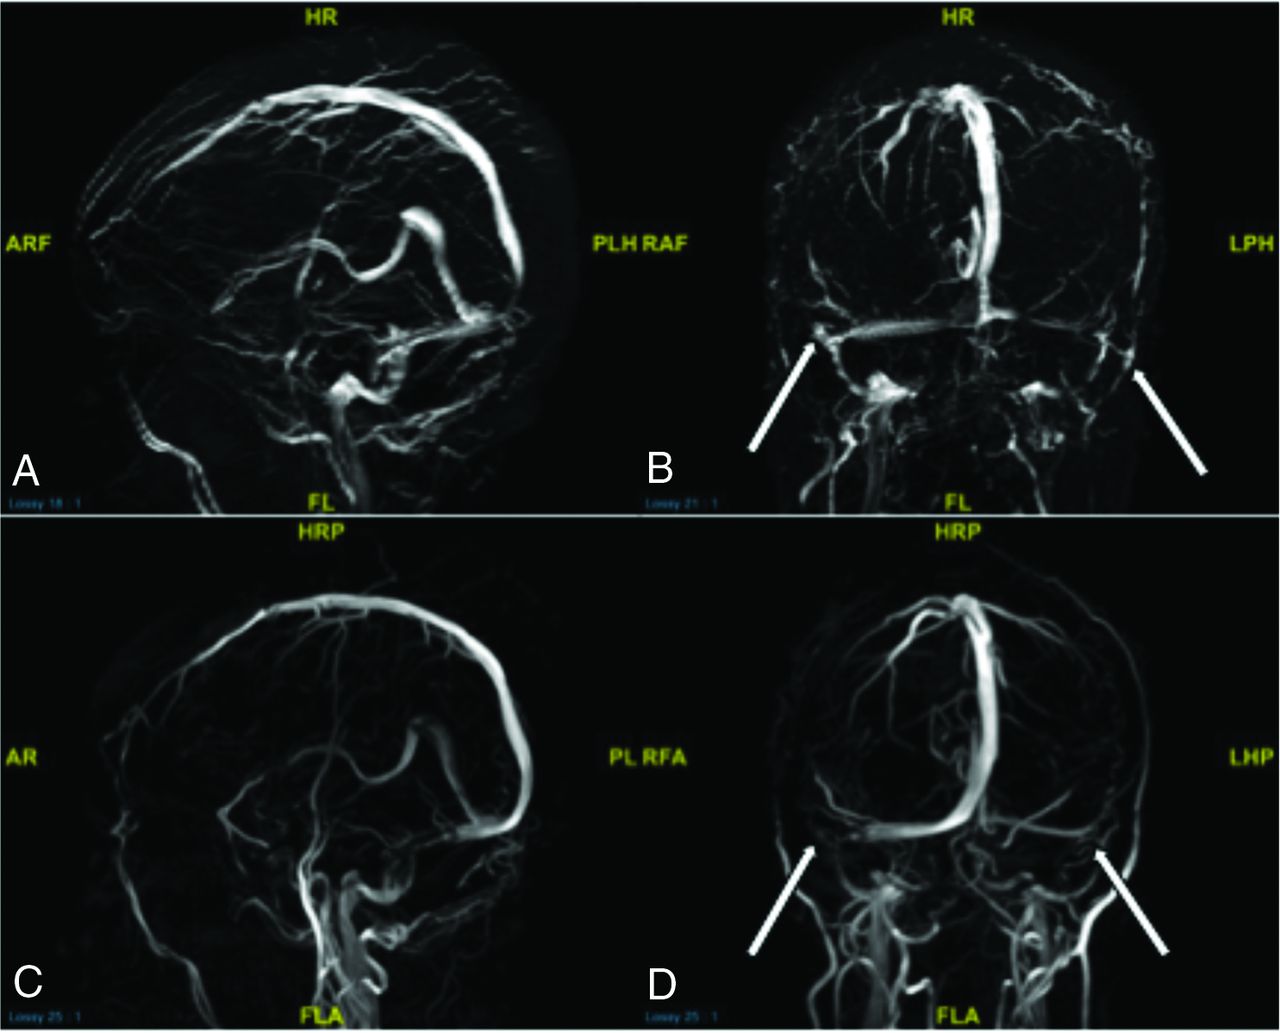

MRV without contrast involves the use of TOF techniques that image the flow of blood in a specific direction, therefore allowing its specificity in looking at the venous system rather than the arteries. TOF allows a physiologic approximation of the dural venous sinus caliber in relation to venous flow through the sinus that can better approximate the true degree of stenosis in a given segment. By administering contrast, one can better characterize a stenosis as the sinus lining and can inspect luminal content with a high special resolution compared with flow-related techniques alone. Contrast-enhanced images also provide the true sinus caliber relative to surrounding calvarial demarcations, an important distinction compared with flow when measuring for hardware sizes, depending on the dural venous sinus segment to be stented. Volume-rendered and 3D reconstructed images from source TOF and contrast-enhanced images were of equal importance in demonstrating a global understanding of the type and location of stenosis (Fig 7).10,11

Comparing TOF sagittal and coronal 3D reconstructions (A and B) and contrast-enhanced sagittal and coronal 3D reconstructions (C and D) from MRV in a patient with idiopathic intracranial hypertension. Note how the TOF images show the patient’s physiologic venous drainage due to properties of TOF imaging, showing only blood draining back to the patient’s heart (veins). Contrast-enhanced imaging, though crisper, shows arteries and veins in the same image. B and D, Arrows point to severe extrinsic stenoses in the bilateral transverse sinus–sigmoid sinus junctions, a common location for idiopathic intracranial hypertension stenosis. Such short-segment severe stenoses appear to simulate the abrupt narrowing commonly seen in short-segment intrinsic stenoses on these 3D reconstructions. However, review of source imaging would demonstrate brain parenchymal narrowing rather than primary arachnoid granulations producing the stenoses. HRP indicates head right posterior; PLH, posterior left head; RAF, right anterior foot; RA, right anterior; FL, foot left; PL, posterior left; RFA, right foot anterior; LHP, left head posterior; LPH, left posterior head; ARF, anterior right foot; AR, anterior right; FLA, foot left anterior; AF, anterior foot.

Confounders in the dichotomous characterization of intrinsic-versus-extrinsic stenosis can be seen. For instance, the degree of extrinsic stenosis can be so severe and short-segmented as to remove the typically seen feature of extrinsic stenosis tapering, giving a false appearance of a rounded filling defect on 3D reconstructions (Fig 7). However, source images would reveal an abrupt change in caliber related to brain parenchyma and not primary intrinsic stenosis lead points. One useful means of distinguishing severe extrinsic-versus-intrinsic stenosis is the continuity of the stenosis in question. Specifically, extrinsic stenosis is typically continuous in length owing to its uniform brain parenchymal extension into the sinus. In contrast, intrinsic stenosis may manifest as discontinuous points of stenosis, depending on the distribution and number of contributory arachnoid granulations.